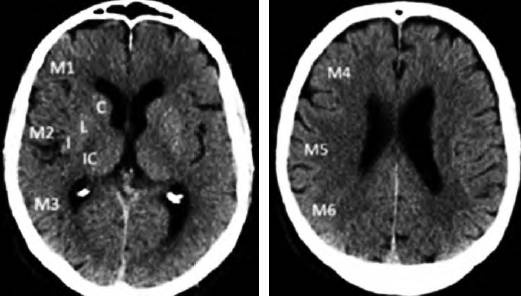

ASPECTS评分是基于NCCT评估MCA区域早期缺血改变简单而系统的一种方法。将MCA供血区各主要功能区分别赋分(4个皮层下区:尾状核C、豆状核L、内囊IC、岛叶I;6个皮层区,标志为M1-M6)(图1),共计10 分,每累及一个区域减去1分,即正常脑CT为10分,MCA供血区广泛梗死则为0分。

图1 ASPECTS评分中大脑中动脉供血区功能分区注:皮层下区:C:尾状核(caudate);L:豆状核(lentiform);IC:内囊(internal capsule);I:岛叶(insular ribbon);皮层区:M1-M6。ASPECTS:Alberta卒中项目早期计算机断层扫描评分

为评估后循环梗死患者早期梗死情况,PUE T Z等建立了评估后循环的AIS预后早期CT评分(pc-ASPECTS)。pc-ASPECTS总分也是10分:双侧丘脑和小脑各1分,双侧大脑后动脉供血区各1分,中脑和脑桥为2分(图2)。

图2 pc-ASPECTS评分中后循环供血区功能分区注:pc-ASPECTS:后循环急性卒中预后早期计算机断层扫描评分